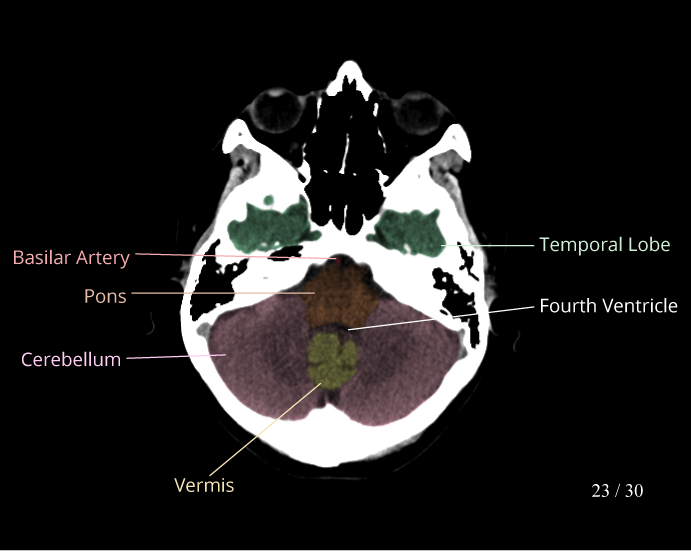

CT Brain Anatomy